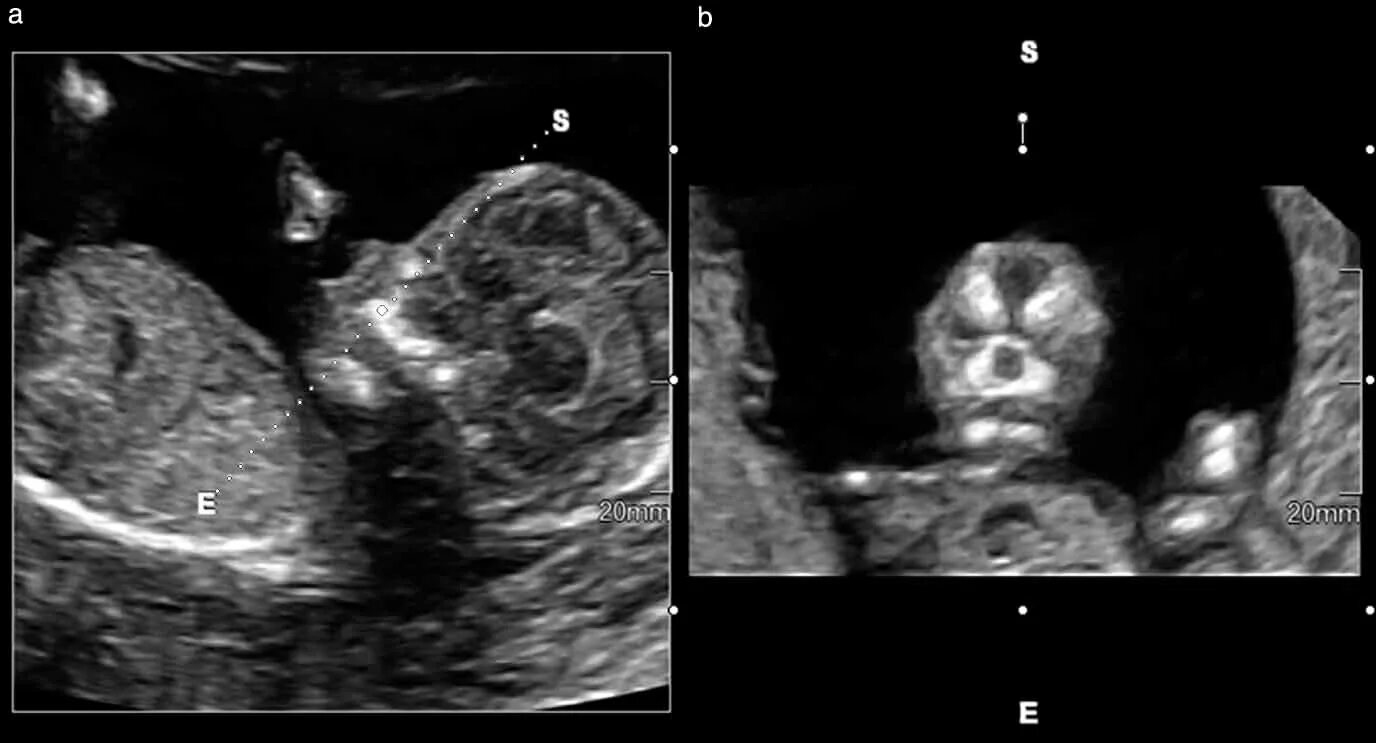

Узи аномалий